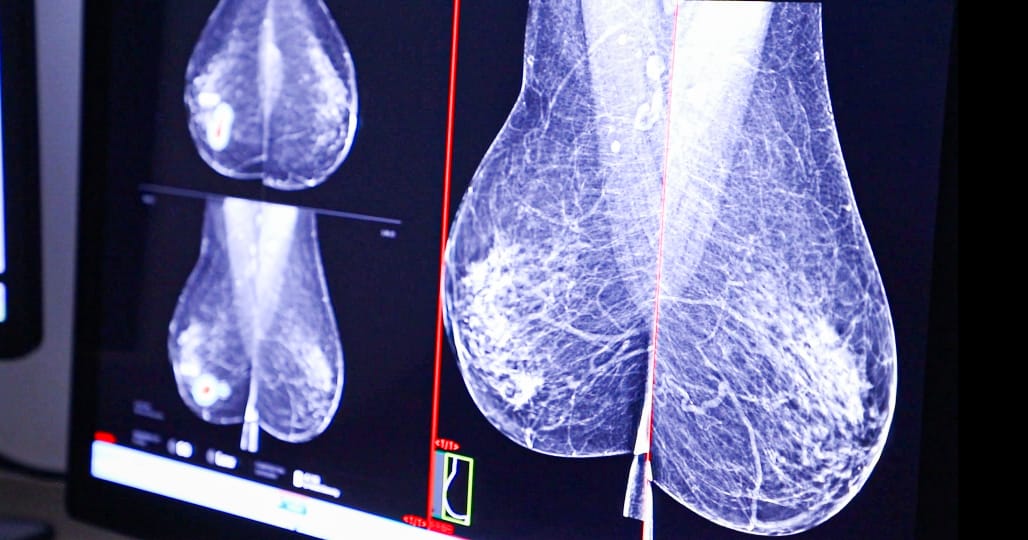

El Dr. Edghar Vän Vega, radiólogo de la Unidad, explicó que este avance reemplaza la técnica tradicional del arpón, que consiste en colocar un alambre dentro de la mama el mismo día de la cirugía, lo que genera incomodidad, ansiedad y limita la flexibilidad en la programación quirúrgica.

En contraste, el reflector puede colocarse días o semanas antes, es mínimamente invasivo y ofrece mayor comodidad para la paciente.

La implantación del reflector se realiza bajo anestesia local utilizando una aguja especial diseñada para este procedimiento. Posteriormente, durante la cirugía, el equipo quirúrgico localiza el reflector mediante una sonda electromagnética, lo que permite identificar con exactitud el sitio de la lesión y realizar resecciones más precisas, preservando mayor cantidad de tejido sano.

Además de los beneficios clínicos, esta innovación optimiza la coordinación entre los servicios de radiología y cirugía, permitiendo una mejor organización del programa de cirugías mamarias, disminuyendo tiempos de espera y mejorando la atención integral a las pacientes.